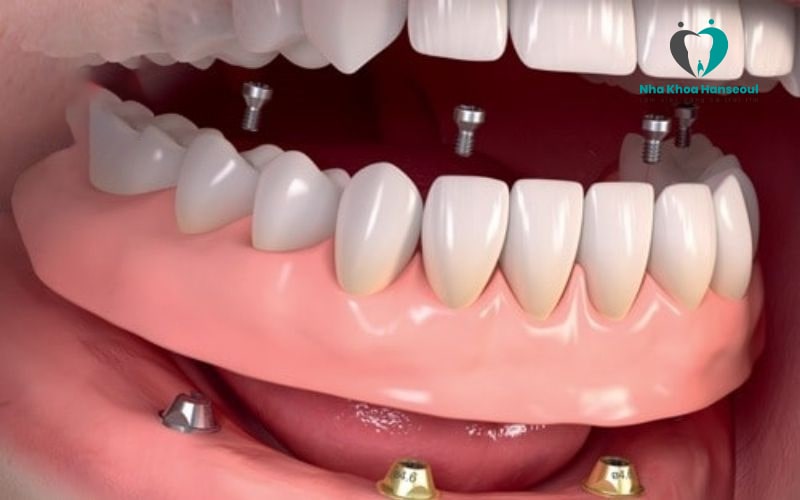

Cấy ghép Implant All On 4 là giải pháp với kỹ thuật cấy 4 trụ Implant vào xương hàm của bệnh nhân. Tuy nhiên, để sử dụng kỹ thuật này thì xương hàm của bệnh nhân phải đủ chắc chắn và đủ dày để hỗ trợ các implant được vững chắc.

Thông thường vị trí đặt trụ implant của kỹ thuật All On 4 thường là: 2 trụ đặt thẳng đứng ở nhóm răng cửa trước. 2 trụ đặt theo góc nghiêng 30 – 45 độ ở nhóm răng hàm. Tuy nhiên, vị trí đặt trụ implant không phải ai cũng giống nhau. Mỗi bệnh nhân sẽ được bác sĩ nha khoa tư vấn cụ thể, chi tiết sau khi thăm khám kỹ càng.

Sau khi cấy implant all on 4, bác sĩ sẽ sử dụng một hàm răng giả hoặc các nhịp cầu răng để phục hình lên phía trên giúp bệnh nhân thuận lợi ăn nhai.